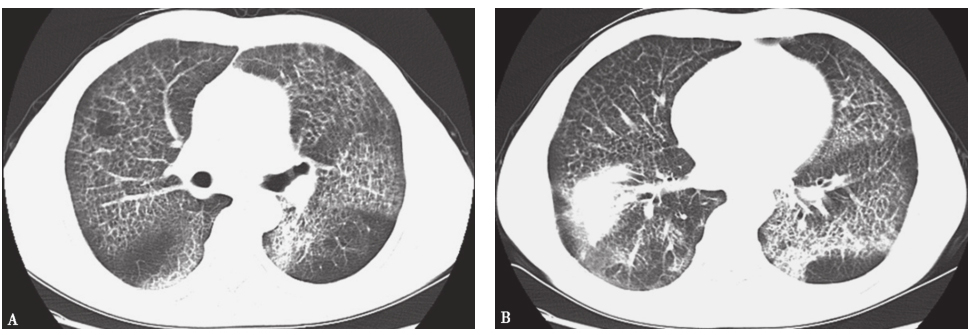

术后,给予减轻肺水肿(呋塞米)、吸氧、抗感染、舒张支气管、祛痰及无创机械通气等治疗,患者感胸闷气促等症状明显缓解。1个月后复查CT提示双肺病灶较前吸收,右下肺大片实变影较前缩小(图6)。患者病情好转出院后,采取吸入GM-CSF治疗,定期随访,状态良好。

图6入院1个月后胸部CT表现